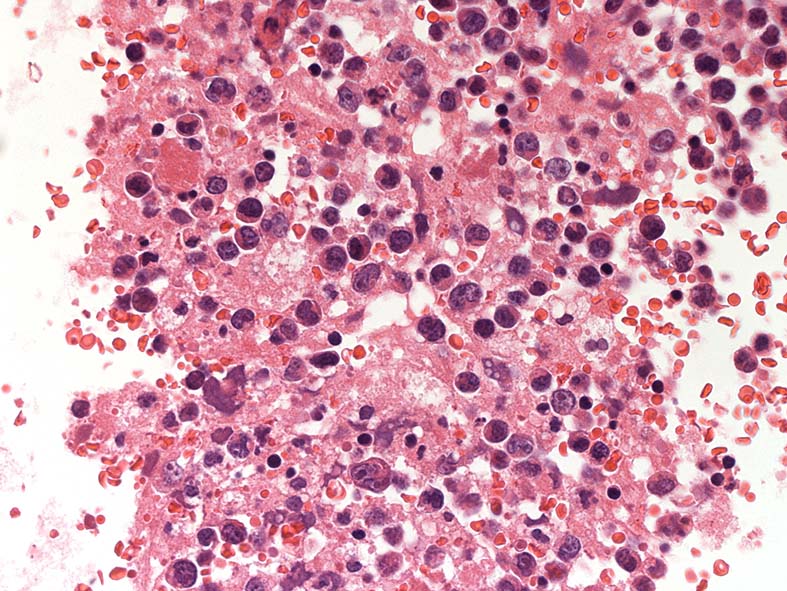

胸水セルブロック: effusion lymphomaの場合, IHCなどの精査はcell brockで行うことになる.

心嚢水セルブロックHE染色: 小リンパ球の3倍から5倍ほどの大型異型細胞が多数増加している. 核は類円形, くびれをもつ多型核が見られ, クロマチンは微細な傾向. 核小体を1-数個もつ.

N/C比は大. 好酸性の細胞質が認められる. セルブロックでは細胞質空胞はあまりめだたない. high-grade lymphoma疑い.